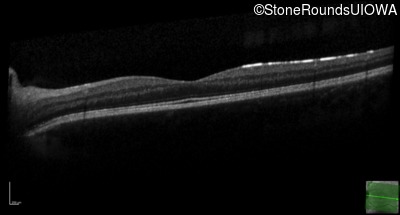

Age at visit: 17 years

OD OS

This 17 year old male had normal vision until about 6 months earlier when he began to lose central vision. The left eye may have been affected prior to the right eye.